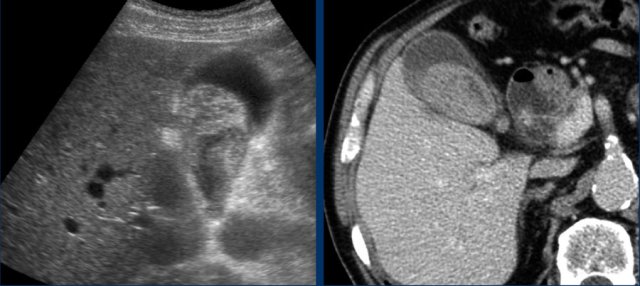

Abscess in the liver adjacent to the gallbladder in acute cholecystitis, visible on both US and CT.

Percutaneous drainage of the gallbladder was done.

The abscess drained itself into the gallbladder lumen.